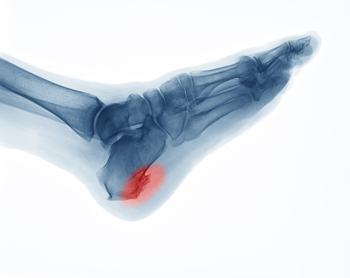

Heel Spurs From Calcium Build-Up

Heel spurs are formed by calcium deposits on the back of the foot where the heel is. This can also be caused by small fragments of bone breaking off one section of the foot, attaching onto the back of the foot. Heel spurs can also be bone growth on the back of the foot and may grow in the direction of the arch of the foot.